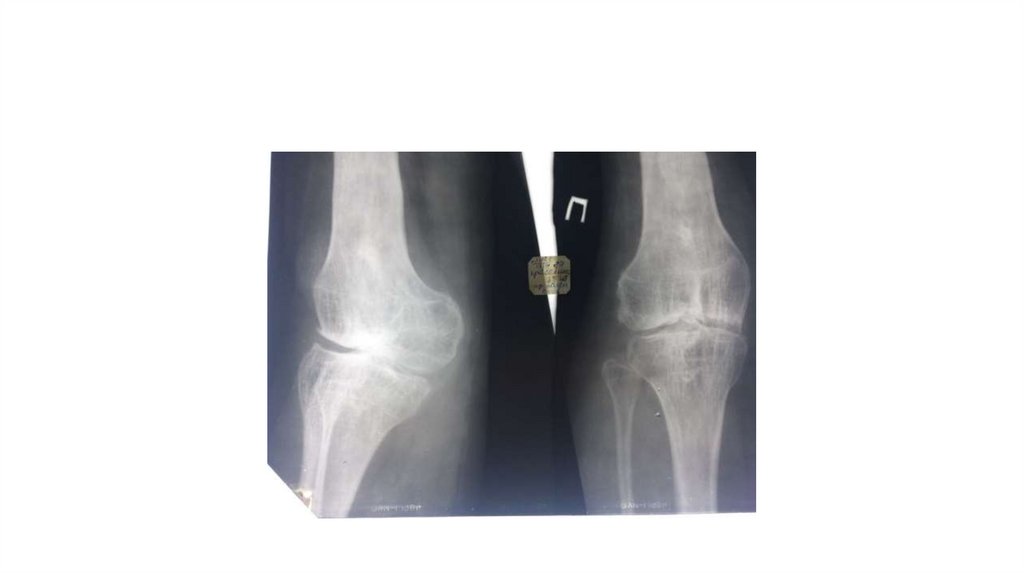

Воспалительные заболевания опорнодвигательного аппарата

1.

Практическое занятие

«Воспалительные

заболевания опорнодвигательного аппарата»